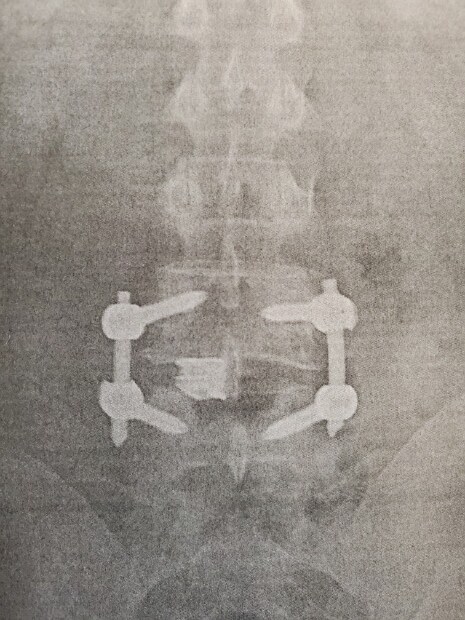

As many of you know, I am having back surgery in a few weeks (Nov 4th), I will have my L4 and L5 fused due to a birth defect.